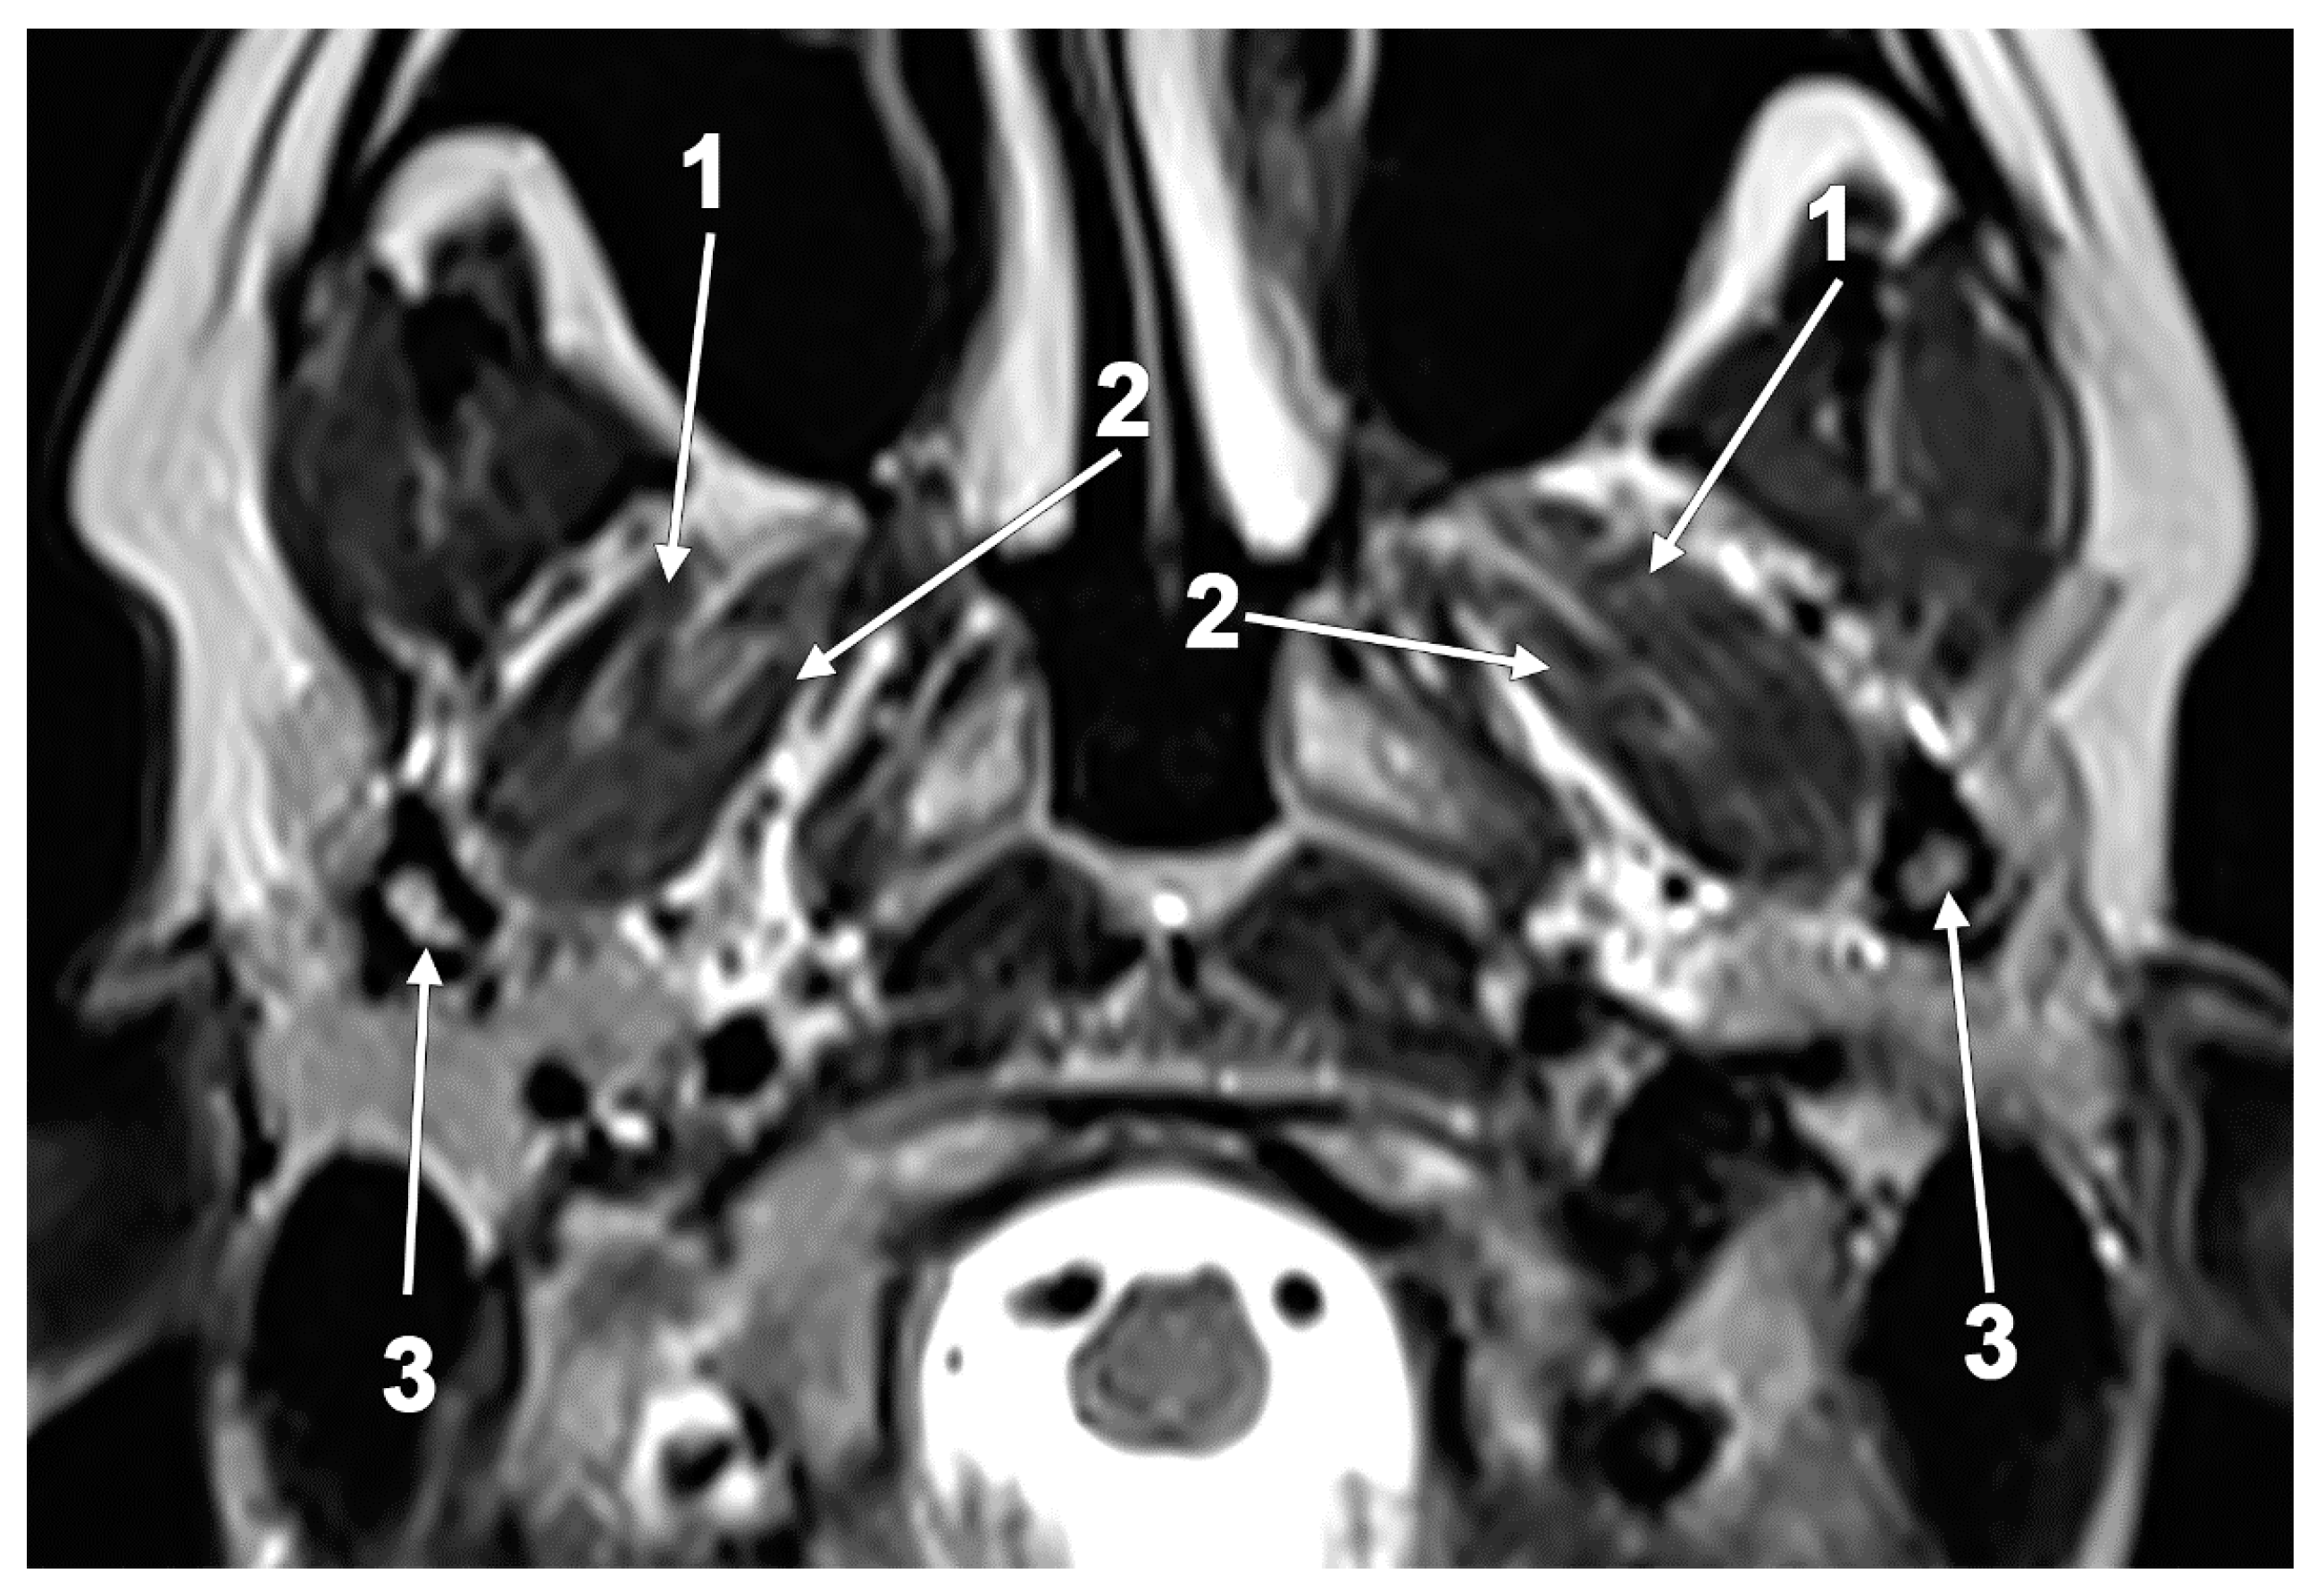

The Atrophy and Hypertrophy of the Lateral Pterygoid Muscle